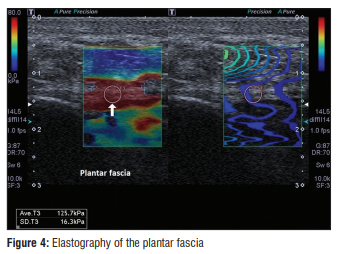

@ DOI: 10.4103/jmu.jmu_2_23 최근에는 여기서 한 단계 더 나아갔습니다. 2021년에 발표된 한 연구에 따르면, '탄성 초음파'라는 새로운 기술로 족저근막염이 생긴 부위의 단단함(경직도)을 측정해보니, 오히려 정상 조직보다 더 무르고 부드러워져 있었다는 사실이 밝혀졌습니다. 밧줄이 탄성을 잃고 흐물흐물해진 상태를 생각하시면 쉽습니다. 심지어 이 방법은 일반 초음파로 두께 변화가 나타나기 전에도 이상을 발견할 수 있어, 조기 진단의 가능성을 열어주었죠. > 발바닥 혹 종양 > > 앞쪽 가운데 바깥쪽 아치 통증 그런데 만약 발바닥에서 무언가 만져진다면 어떨까요? **"원장님, 발바닥에 혹이 만져지는데*

@ DOI: 10.4103/jmu.jmu_2_23

앞서 소개해드린 2023년 논문에 따르면,

초음파를 보면서 주사하는 것이

단순히 만져보고 주사하는 것보다

치료 결과가 우수하며,

주변 신경이나 혈관을 건드리는 위험을

피할 수 있다고 강조하기도 했습니다.